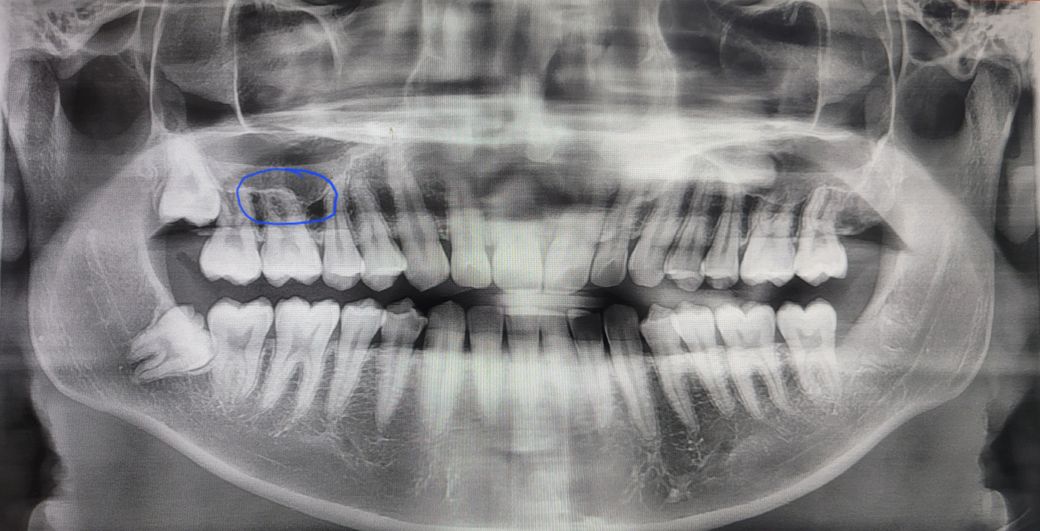

참고사진은 치과에서 찍은 사진입니다

파란 동그라미 부분이 욱욱거립니다.

• 1번 째 사진

치과에서 이상이 없었다면, 상급병원 급의 이비인후과에서 상악동 주변의 이상소견에 대해 진료를 받아보시는 것이 좋겠습니다.